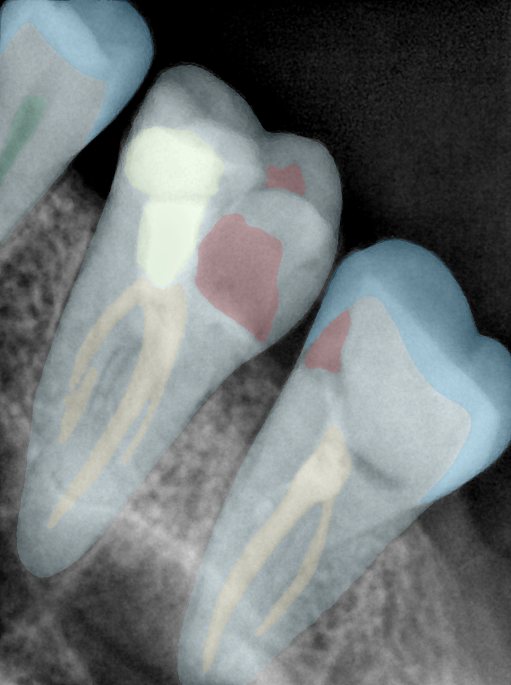

第二版算法问题测试

| 第一版 | 第二版 | 是否解决 | |

|---|---|---|---|

![]() | ![]() ![]() 边角识别有问题 龋齿识别不全 牙髓识别不全 | ![]() | 解决 |

![]() | ![]() 边角识别有问题 识别信息有误 自查(牙冠识别不全) | ![]() | 解决 |

![]() | ![]() ![]() 边角识别有误 大范围填充识别遗漏 | ![]() | 解决 |

![]() | ![]() 识别信息不全 | ![]() | 解决 |

![]() | ![]() ![]() 边角问题 牙胶识别不全 牙冠识别不全 | ![]() | 解决 |

![]() 换图片 | ![]() | ![]() 牙冠部分稍微白了一些就识别成小范围修补,部分判断异常 | 部分解决,修复类略敏感,牙冠部分稍微白了一些就识别成小范围修补,部分判断异常。 |

![]() | ![]() ![]() 牙冠识别不全 牙髓不全 根尖炎龋齿识别有误 | ![]() | 解决 |

![]() | ![]() | ![]() | 解决 |

![]() 换图片 | ![]() | ![]() | 解决 |

![]() | ![]() 牙冠识别有误 | ![]() | 解决 |

![]() 换图片 | ![]() ![]() 边角识别有误 | ![]() 修复类敏感 | 部分解决,图像过白,导致修复类判断异常。 |

![]() 换图片 | ![]() 牙冠识别不全 | ![]() 修复类敏感 | 部分解决,图像过白,导致修复类判断异常 |

结论:修复类出现了不鲁棒的情况,后续需要加入轮廓的扩充数据进行增强。